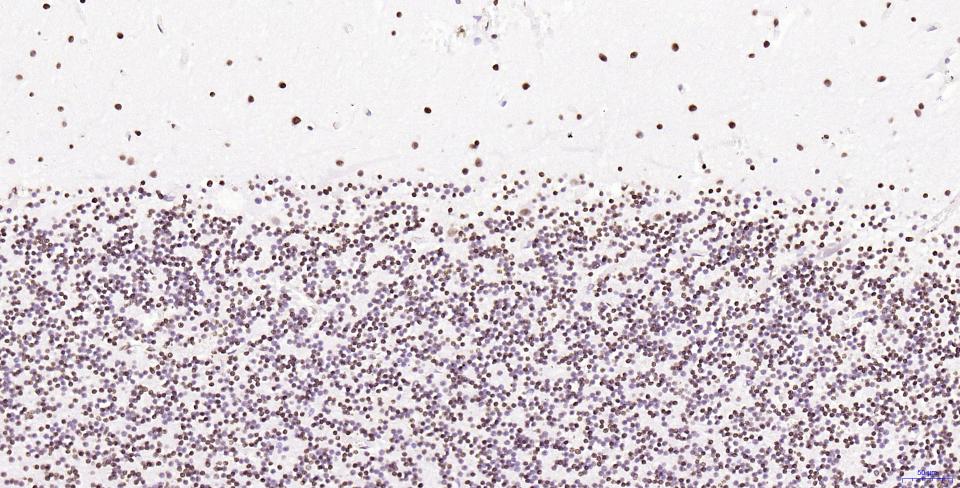

Paraformaldehyde-fixed, paraffin embedded Human Cerebellum; Antigen retrieval by boiling in sodium citrate buffer (pH6.0) for 15 min; Antibody incubation with Histone H2A.X Monoclonal Antibody, Unconjugated(bsm-61080R) at 1:200 overnight at 4°C, followed by conjugation to the SP Kit(Rabbit, SP-0023) and DAB (C-0010) staining.